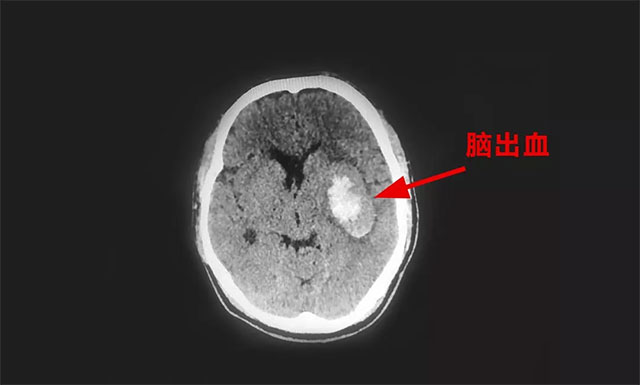

經(jīng)頭顱CT檢查,汪先生被診斷為左側(cè)基底節(jié)區(qū)出血。除了右側(cè)肢體癱瘓,患者還出現(xiàn)了精神躁動、言語不清的情況,病情快速加重。

▲ 患者左側(cè)基底節(jié)區(qū)二次出血伴水腫帶環(huán)繞